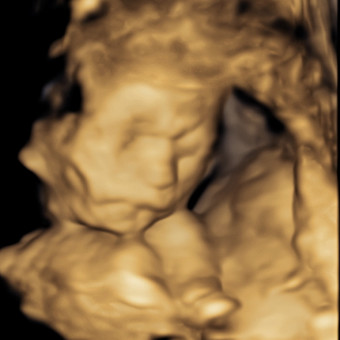

Karlee & Travis Baby 2

Karlee Burke & Travis Wilson

Karlee and Travis are welcoming another baby girl.